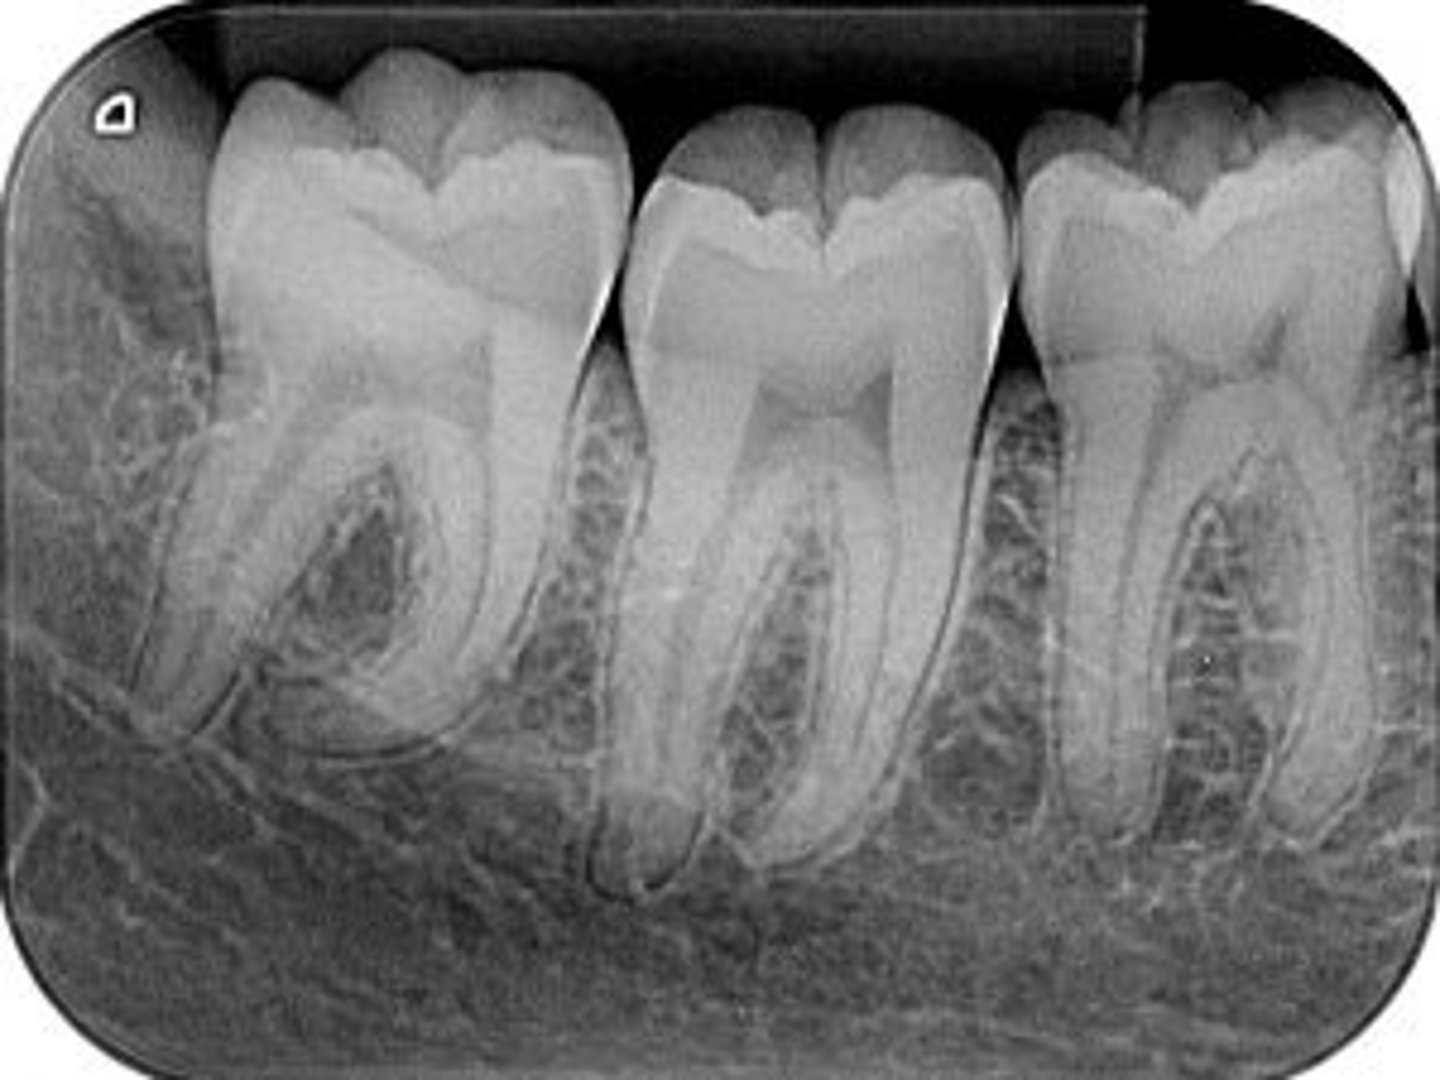

periapical

radiographic image showing the crown, root tip, & surrounding structures

periapical radiographs used to detect:

any abnormalities of the root structure & surrounding bone structure